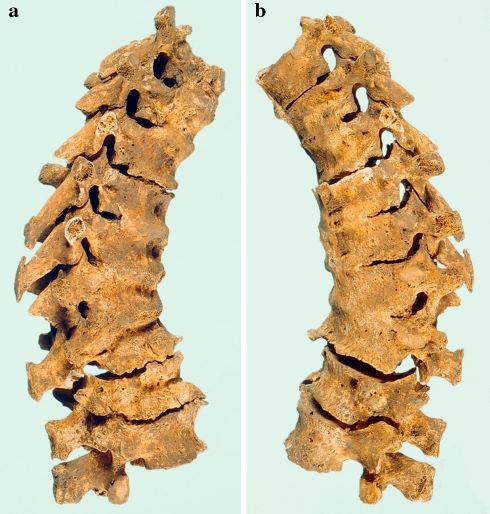

DISH je sistemsko oboljenje koje dovodi do okoštavanja ligamenata, prvenstveno duž kičmenog stuba, ali i na mestima pripoja mišića i tetiva. Najčešće zahvata prednji uzdužni ligament kičme, stvarajući karakterističan izgled „voska koji se topi“, poznat iz savremene radiologije. Iako se često smatra „tihoj“ bolesti, u uznapredovalim stadijumima može ozbiljno ograničiti pokretljivost, izazvati bol, probleme sa disanjem, pa čak i povećati rizik od teških preloma nakon minimalne traume.

Neki od analiziranih skeleta iz Mastrihta pokazuju ekstremne oblike bolesti. Kod pojedinaca je došlo do potpunog ukočenja grudnog koša, što je značajno ograničavalo disanje i fizičku aktivnost. Kod drugih su okoštavanja zahvatila ramena i druge periferne zglobove, verovatno uzrokujući bol i smanjeni obim pokreta.

Ovi primeri jasno pokazuju da DISH nije uvek benigna pojava bez kliničkog značaja. Naprotiv, u uznapredovalim slučajevima mogla je ozbiljno narušiti kvalitet života, čak i u periodima kada medicinska pomoć gotovo da nije postojala.